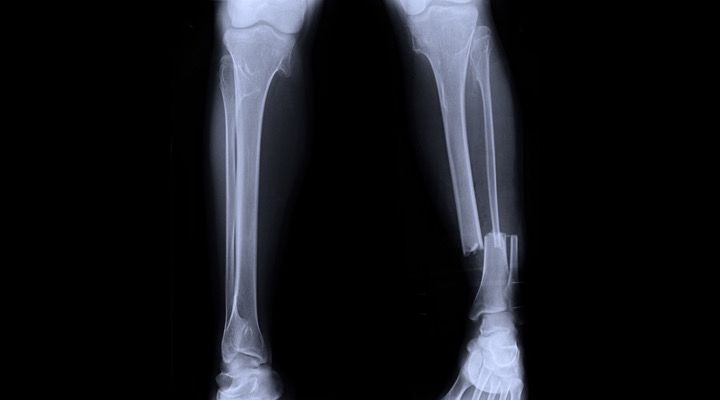

Flopped Foot

After giving Robinson some pain medication, the ambulance crew was able to get the boot off. After removing it they knew just how bad the break was. “When they did my foot just flopped to the side in a horrible shape,” Robinson said.